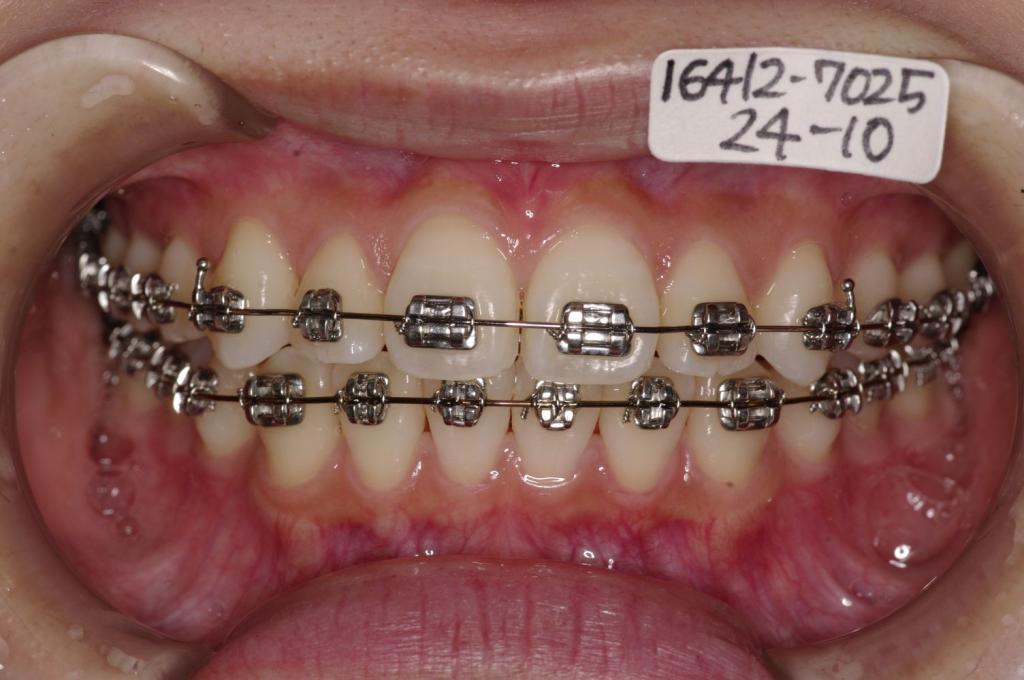

装置の種類及び治療法 診断:叢生

治療方法および装置:マルチブラケット装置

High pull J-hook headgear

抜歯:非抜歯

装置写真

治療前

歯並び・咬み合わせ・八重歯・乱杭歯の矯正治療前口内写真NO.1234